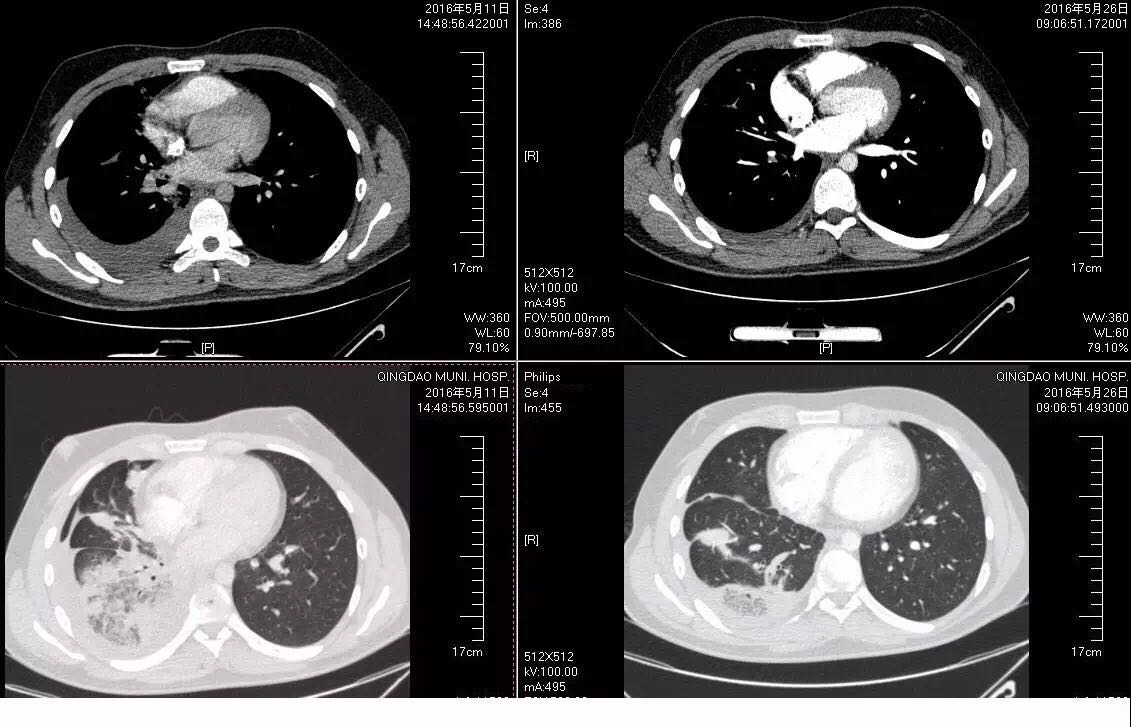

2周前患者因受凉出现咳嗽,咳少量黄黏痰,自诉感发热,未测体温,初无胸痛、胸闷,无咯血、盗汗,自服感冒灵、退热药后自觉好转。1周前患者出现右季肋区疼痛,为持续性钝痛,吸气及咳嗽时加重,仍咳少量黄痰,无胸闷、喘息,遂就诊于我院急诊,查血常规WBC 9.54×109/L, C反应蛋白10.65mg/L;胸部CT提示右下肺磨玻璃样渗出影,诊为社区获得性肺炎,急诊室给予阿奇霉素联合头孢西丁抗感染治疗,病人每日输液后返家,未规律监测体温,1周后复查胸部CT示右下肺病灶较前进展,累及胸膜,少量胸腔积液(见图1),并出现胸痛加重,今为进一步治疗收入我科。

图1 入院查体T: 37.8 ℃,听诊右肺呼吸音低,未闻及干湿性啰音,心率68次/分。 诊断: 社区获得性肺炎,非重症 ; 2.胸膜炎; 3.胸腔积液。 病人青年男性,考虑抗感染力度不够、覆盖不足或结核可能,另外也考虑到我国支原体对阿奇霉素耐药率高的问题,给予磷霉素联合米诺环素抗感染,辅以止咳、化痰等治疗。病人于入院次日晨咳鲜红色血痰10ml,体温升至38.9℃,加用奥司他韦抗病毒,并予云南白药止血对症治疗。同时完善相关检查,降钙素原0.1ng/ml;血常规:WBC 10.78×109/L,C反应蛋白109.60mg/L;D-二聚体定量3.45ug/ml,我院正常值为0---0.5 ug/ml 白蛋白43.28g/L;血沉61.00mm/H; ANA谱及ANCA均未见异常;肺炎支原体抗体阴性;肺炎链球菌抗原定性阴性;24h痰液未找到抗酸杆菌。 此后病人发热、咯血无缓解,PPD试验阴性,行胸腔超声检查,报胸腔积液,液深1.8cm,建议胸腔穿刺、支气管镜检查进一步明确,病人家长均拒绝。考虑病人年少,无持续卧床史,双下肢无水肿,心电图无异常改变,D-二聚体升高考虑感染所致,加用头孢他啶进一步覆盖G-杆菌。病人体温峰值出现下降,咯血、胸痛仍无好转,入院第5天复查血常规:WBC 7.00×109/L,C反应蛋白149.16mg/L;D-二聚体定量3.95ug/ml;肌钙蛋白、BNP正常;血气分析示pH为7.52,PaO2为136mmHg,PaCO2为30.9mmHg(吸氧流量为2L/分);痰培养、血培养均为阴性。 再次评估病情,经较强抗感染治疗患者仍有发热、胸痛、咯血,D-二聚体较前升高,追问病史近期有夜间长时间端坐玩电脑诱因,考虑肺栓塞不能排除,停用云南白药。病人家长初拒绝CTPA检查,完善下肢血管超声未见异常,遂先行超声引导下胸腔穿刺,抽出不凝血,胸水常规:白细胞 1878×106/L,N80%,蛋白定性实验4+;胸水腺苷脱氨酶18.02U/L。再次与病人家长沟通后于入院第6天行CTPA检查,提示右下肺动脉栓塞,右肺片状影及胸腔积液均较前加重(见图2、3)。